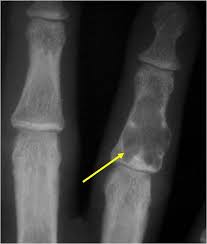

Tumores musculo esqueletico del miembro superior

Los tumores en el miembro superior requieren de un estudio y un tratamiento adecuado. Se tiene que iniciar con un buen diagnóstico, lo que incluye un examen físico minucioso, complementado con examenes radiograficos, tomografias, como ecografias o resonancias. con la finalidad de tener un estadiamiento que es el grado y extensión de la lesión. La mayoria de los tumores de la mano son benignos, pero todo requieren de ser evaluados por médicos con experiencia.